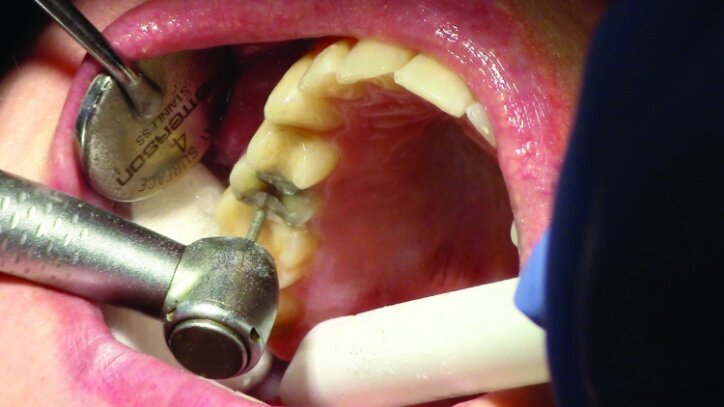

Gross occlusal reduction was completed using a KS7 bur to the depth cuts (Figs. 4–8b, 9c). Adequate clearance was verified with a 2 mm prep check from Common Sense Dental Products.

After gross occlusal reduction was completed, the remaining enamel ring was measured (Figs. 9a, b). The enamel rings were noted to be 1.5 mm, and the teeth were prepared for adhesively retained restorations. If the enamel rings were less than 1 mm, the teeth would have been prepared on the axial walls to create retention for cohesively retained crowns.

The remainder of the existing composite resin in #3 and the amalgam in #4 were removed. The occlusal surfaces of the preparations were blended into the interproximal areas using a KS2 bur to create smooth preparations (Figs. 10–15c). There was no retention or resistance form prepared to retain the restorations.